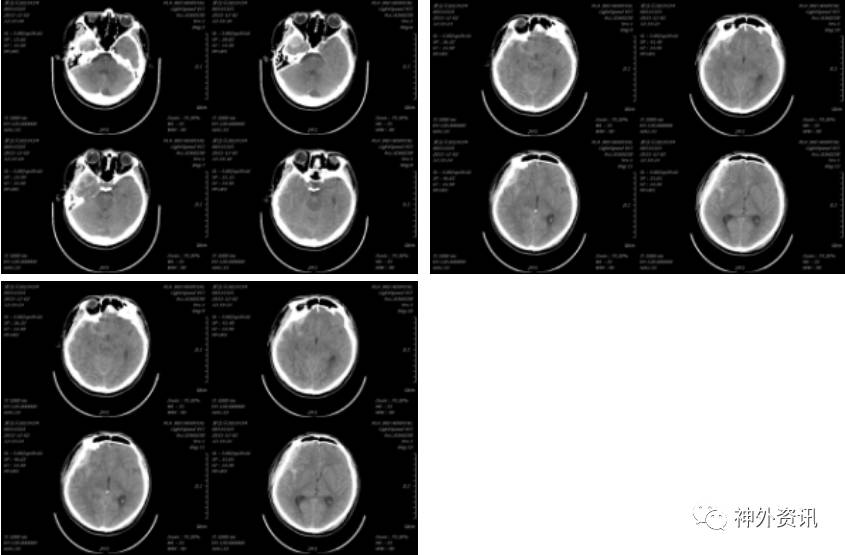

患者于2016-02-03能发简单“咿、啊”等音,但2016-02-26患者出现反应迟钝,大小便失禁等症状,复查头颅CT示(2016-02-26 14:25):

于2016-03-04在全麻下行颅骨钛网修补术,2016-03-05复查头颅CT示(2016-03-05 10:02):

术后患者反应迟钝、大小便失禁等症状缓解不明显,于2016-03-15在全麻下行脑室-腹腔分流术,术后复查头颅(2016-03-16 11:59)示: